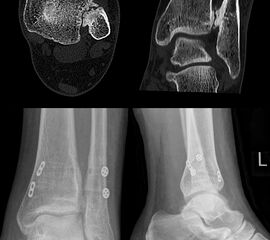

Grass et al. 58 schlugen eine chirurgische Rekonstruktion mit einem Peroneus longus Span vor. Bei diesem Eingriff werden alle drei Anteile des Syndesmose durch einen freiem Peronaeus longus Span augmentiert (Abbildung 10).

Andere Autoren beschreiben eine anatomische Rekonstruktion mit Fixation der Syndesmose über mehrere Monate 5960, was sich auch in unseren Händen bewährt hat. Nach einer offenen anatomischen Rekonstruktion der Syndesmosenbänder bevorzugen wir zur Sicherung eine Kombination aus einem dynamischen Stabilisierungssystem (z.B. Tight-Rope) und einer Stellschraube. Nach 8 Wochen wird die Stellschraube entfernt, die in der ersten Phase die Fibula sowohl gegen eine ventrodorsale Translation, als auch gegen eine Rotation sichert. Nach Entfernung der Stellschraube wird mit dem Belastungsaufbau begonnen. Das dynamische Stabilisierungssystem kann belassen werden und sorgt für eine stabile Ausheilung bzw. Vernarbung der Syndesmosenbänder. Auf Wunsch des Patienten oder bei Hautirritationen kann das Suture-Button-System nach 12 Monaten entfernt werden. Aktuell fehlen qualitativ hochwertige Studien um das ein oder andere Verfahren zu favorisieren.